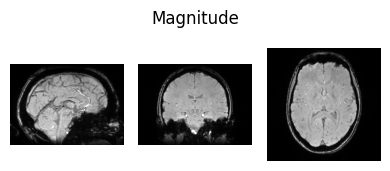

show_nii(glob("bids/sub-*/ses-*/anat/*mag*T2starw*nii*")[0], title="Magnitude", vmax=500)